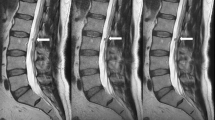

Sequences acquired. On top (A–E) DLR algorithm. A, D and E T2W FSE; B T1W FSE; C STIR. Below (F–J) conventional protocol. F, I and J T2W FSE; G T1W FSE; H STIR. DLR improves signal-to-noise ratio (SNR), contrast-to-noise ratio (CNR) and image sharpness and reduces artefacts. DLR images appear smoother than standard

The CNR of the images reconstructed with DLR algorithm was superior to standard protocol in both T2W FSE sagittal (6.15 ± 7.45 vs 2.20 ± 5.95, p < 0.001) and axial images (10.38 ± 4.54 vs 4.91 ± 2.69, p < 0.001) whereas no significant differences were reported for T1W FSE (2.67 ± 8.98 vs 4.91 ± 5.37, p = 0.170) and STIR images (2.69 ± 7.76 vs 2.25 ± 5.52, p = 0.610). Table 3 summarizes SNR and CNR values.

Qualitative analysis showed a greater overall quality in all sequences (all p < 0.001) of the images reconstructed with DLR algorithm than standard protocol (median: 4, IQR: 4–5; and median: 5, IQR: 4–5; for reader 1 and reader 2, respectively), with an inter-rater agreement of 0.83 (0.78–0.86). For reader 1, highest quality was found for sagittal STIR (median: 5, IQR: 4–5) and axial T2W FSE (median: 5, IQR: 4–5) and for reader 2 was found for sagittal T1W FSE (median: 5, IQR: 4–5) and T2W FSE (median: 5, IQR: 4–5). Table 4 summarizes scores of the two readers.

Pathologic findings and diagnostic confidence

The frequency of pathologic findings did not differ between DLR and standard protocol; findings reported were protrusions (n = 11), Modic changes (n = 8), haemangioma (n = 7), Schmorl’s nodes (n = 4) and incidental findings (renal and adnexal cysts, n= 4), all p > 0.05. Figure 4 and Table 5 summarize pathologic findings reported. None of the findings in both protocols had artefacts (i.e. aliasing or banding artefacts) that might hinder image evaluation.

The diagnostic confidence was the same for both DLR algorithm (median: 5, IQR: 4–5) and for standard protocol (median: 5, IQR: 4–5), p > 0.05.